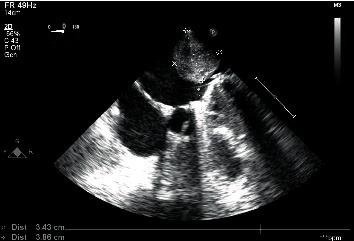

Malignant cardiac tumors are extremely rare, representing only 25% of all cardiac tumors, and angiosarcoma is the most common subtype. Myxofibrosarcomas are one of the rarest forms of cardiac malignant tumors. These tumors can silently grow and produce no or few symptoms until the tumor is large enough to obstruct blood flow. The definitive treatment is negative margin resection, if possible. Most cardiac tumors have a limited response to chemotherapy and radiotherapy. Therefore, surgical treatment is considered the best option. Our patient is a 57-year-old Caucasian postmenopausal female who presented with dyspnea, shortness of breath, and fatigue. Echocardiography confirmed the presence of a mass in the left atrium. A median sternotomy was performed with aortic and bicaval cannulation. Right atriotomy was performed, and the left atrium was exposed through the transseptal approach. A rounded smooth-surfaced mass was found in the left atrium that was 3.5 × 4.5 cm in size. The mass had a prominent and firm attachment point with a wide-based stalk in the pulmonary vein-right atrium border area. The tumor was completely excised, and the excision point was strengthened with a running suture. The following pathologic diagnosis was finally made: myxofibrosarcoma, FNCLCC (National Federation of Cancer Centres) Grade 2. Immunohistochemistry showed positivity for Epithelial membrane antigen (), desmin, calretinin, Ki67, Smooth Muscle Actin (), and S100. Given the rarity of cardiac malignant tumors, we thought preoperatively that this particular tumor could be a myxoma although it did not have the classical attachment point with a stalk at the interatrial septum. Our case is an example of how fast a cardiac sarcoma can grow. Nine months before the presentation, the patient underwent an echocardiography that did not show any signs of tumor growth. The estimated time of growth was 9 months or less. We followed our patient, performing a computer tomography scan and echocardiography 1 month after surgery, and these did not show any signs of tumor growth.

恶性心脏肿瘤极为罕见,仅占所有心脏肿瘤的25%,血管肉瘤是最常见的亚型。黏液纤维肉瘤是心脏恶性肿瘤中最罕见的形式之一。这些肿瘤可悄然生长,在肿瘤大到足以阻塞血流之前不产生或仅产生很少症状。如果可能,确定性治疗是切缘阴性切除。大多数心脏肿瘤对化疗和放疗反应有限。因此,手术治疗被认为是最佳选择。我们的患者是一名57岁的白种人绝经后女性,表现为呼吸困难、气短和乏力。超声心动图证实左心房存在肿块。采用主动脉和双腔静脉插管进行正中胸骨切开术。进行右心房切开术,并通过经房间隔途径暴露左心房。在左心房发现一个大小为3.5×4.5厘米的圆形、表面光滑的肿块。该肿块在肺静脉 - 右心房边界区域有一个突出且牢固的附着点,有一个宽基底蒂。肿瘤被完全切除,切除点用连续缝合加强。最终做出如下病理诊断:黏液纤维肉瘤,法国国立癌症中心联合会(FNCLCC)2级。免疫组化显示上皮膜抗原()、结蛋白、钙视网膜蛋白、Ki67、平滑肌肌动蛋白()和S100呈阳性。鉴于心脏恶性肿瘤的罕见性,我们术前认为这个特殊肿瘤可能是黏液瘤,尽管它没有在房间隔处带有蒂的典型附着点。我们的病例是心脏肉瘤生长速度有多快的一个例子。在就诊前九个月,患者接受了超声心动图检查,未显示任何肿瘤生长迹象。估计生长时间为9个月或更短。我们对患者进行了随访,术后1个月进行了计算机断层扫描和超声心动图检查,这些检查未显示任何肿瘤生长迹象。